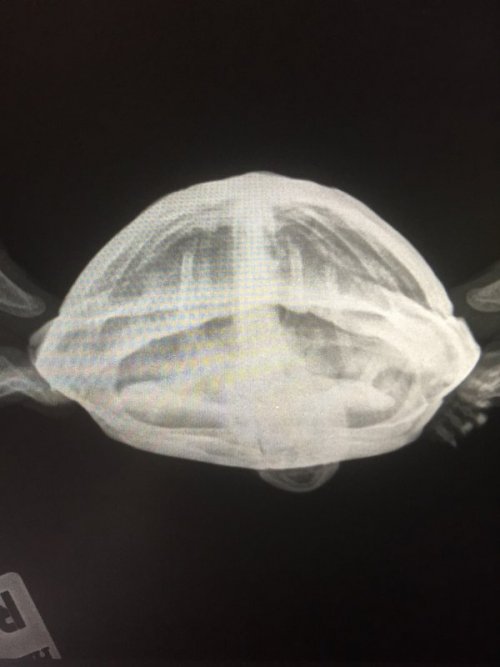

Dmitrii Ваше имя: Дмитрий Локация: Россия. Благовещенск Амурская область Опубликовано: 3 января 2021 Опубликовано: 3 января 2021 Здравствуйте. Заболела черепаха. Два месяца ничего не ест. Началось всё в октябре. Я открыл перегородку между самцом и самкой, чтоб поплавали (закрываю чтоб не дрались), самец погонялся за самкой с открытым ртом, хотел укусить, он так всегда делает, после он вылез на остров и не хотел слазить, и вид у него был такой будто ему плохо стало. После он стал плавать как поплавок и не опускался на дно, потом вообще стал тонуть как камень и перестал есть (вообщем он не ест уже больше двух месяцев). Всю ночь лежал на суше, в воду не лез. В группе в вк посоветовали проколоть кальций борглюконат , элеовит, морфлаксин, и рингера локка (уколы я проколол две недели) и сразу сделать снимок. На снимке сказали, что пневмании не обнаружено. После я обратился в ветклинику, где прописали далее колоть всё тоже самое + ванночки с ромашкой, преднизалон, фуросемид, ронколейкин и сделали снимок (второй) там обнаружили пневманию.(хотя возможно жидкости на снимке, это последствия многих уколов. в день много жидкостей закачивал в него). После курса лечения, сделали снимок (третий), сказали что положительная динамика есть, колим уколы дальше. Но он всё равно не ест и не плавает. анкета: 1. Благовещенск. Амурская область. 31 год. 2. красноухая черепаха 3. аквариум на 200 литров. 4. лампа накаливания 11 часов работы; УФ 10% SERA 11 часов работы стоит с сентября 2020; берег стеклянный с резиновым покрытием; внешний фильтр; нагреватель воды поставил с октября; 5. грунт отсутствует 6. температура воды 28-29 гр. нагреватель включаю ночью. на суше 30-31 гр. 7. питается речной рыбой-ротан, гальян, как дал ротана так он и перестал есть, сухой корм рептомин и sera раз в 3 недели, консервированный сверчок, зофобас, львинка, мучной червь, говяжья печень раз в две недели, очень редко улитки. 8. 9 лет, 500 грамм, 14 см, не ест уже 2 месяца, лечения не помогают, диагноз точный не известен, проявилась с 20 октября, на еду странная реакция, начинает чесать глаза, глубоко дышать, отворачиваться, открывать рот будто тошнит от еды, появилось вздутие, хвост немного увеличился. в воде тонет как камень, падает на спину. 9. обращался в группу по красноухим черепахам в вк и вет клинику АМУРВЕТ Виолетта Николаевна, уколы кальций борглюконат, элеовит, рингера локка, фурасемид, ронколейкин, преднизалон, марфлоксин - дозировку рассчитывал у Вас на сайте по калькулятору. Уколы делаю уже более полтора месяца.

Dmitrii Ваше имя: Дмитрий Локация: Россия. Благовещенск Амурская область Опубликовано: 3 января 2021 Автор Опубликовано: 3 января 2021 в группе вк прописали колоть Байтрил раз в день в плечо ( про него забыл написать) 10 уколов, кальций 0,71 мл через день подкожно 10 уколов, элеовит два укола раз в неделю. дозировки не помню рассчитывал по калькулятору на сайте. Как проколол все эти уколы, назначили марфлоксин (вместо байтрила) 0,12 мл, 12 дней. первый рентген я скину, остальных нет. После лечения ничего не изменилось, я поехал в венклинику. Сделали второй раз рентген. сказали пневмания (как я и писал мне показалось жидкость обнаружена на снимках из за уколов), там назначили фурасемид 0,1 мл, рингер локка 7 дней, ронколейкин 0,1 мл. через день 6 уколов, преднизалон 0,1 мл. Третий раз в ветклинике сделали снимок, сказали что есть улучшения, но возил черепаху не я, а жена, прописали колоть фурасемид 0,1 мл 1р в 3 дня, предгизалон 0,05 мл 1р в день 2 недели, морфлаксин 0,12 мл 2 недели каждый день, рингера локка 2,3 мл через день. Еду предлагал разную, сверчка, зофобоса, червей, рыбу речную и даже морскую (обычно морскую я ему не даю), два дня давал ему креветку (их я ему обычно не даю вообще, но знаю что для него это лакомство) он и от них отказался. я сперва подумал что это из за карася, костей много, и я их никогда не давал, после них он стал так себя вести. либо это совпадение. Просто пневмания это странно в моих условиях. вода всегда 26-27 гр (потом как он заболел поставил обогреватель), лампа накаливания на 60 Вт, на суше температура 28-30 градусов. в квартире тепло. по полу не гуляет.

Консультанты moth Ваше имя: Мария Локация: Москва Опубликовано: 3 января 2021 Консультанты Опубликовано: 3 января 2021 @Dmitrii врач тему посмотрел, нужно сделать рентген дорзо-вентральная и правая латеральная проекции. По первому снимку у черепахи кости почти прозрачные и на грани перелома из-за хрупкости. Возможный диагноз паралитический илеус или что-то подобное, точнее с текущей информацией не сказать. Препараты все отменить из тех, что были назначены. Сделать рентген как можно быстрее и начать уколы кальция. У Вас остался Борглюконат или Глюконат? Также нужен Элеовит. Напишите какой кальций есть или какой можете купить - я распишу курс по дозировкам, что дал врач. Черепахе 3 раза в день по 30 минут делать вибротерапию. Положить в небольшой контейнер без воды и поставить на сильно вибрирующий прибор. Если ничего такого нет - можно на телефон в режиме максимальной вибрации. Стиральная машинка на отжиме на макс оборотах.